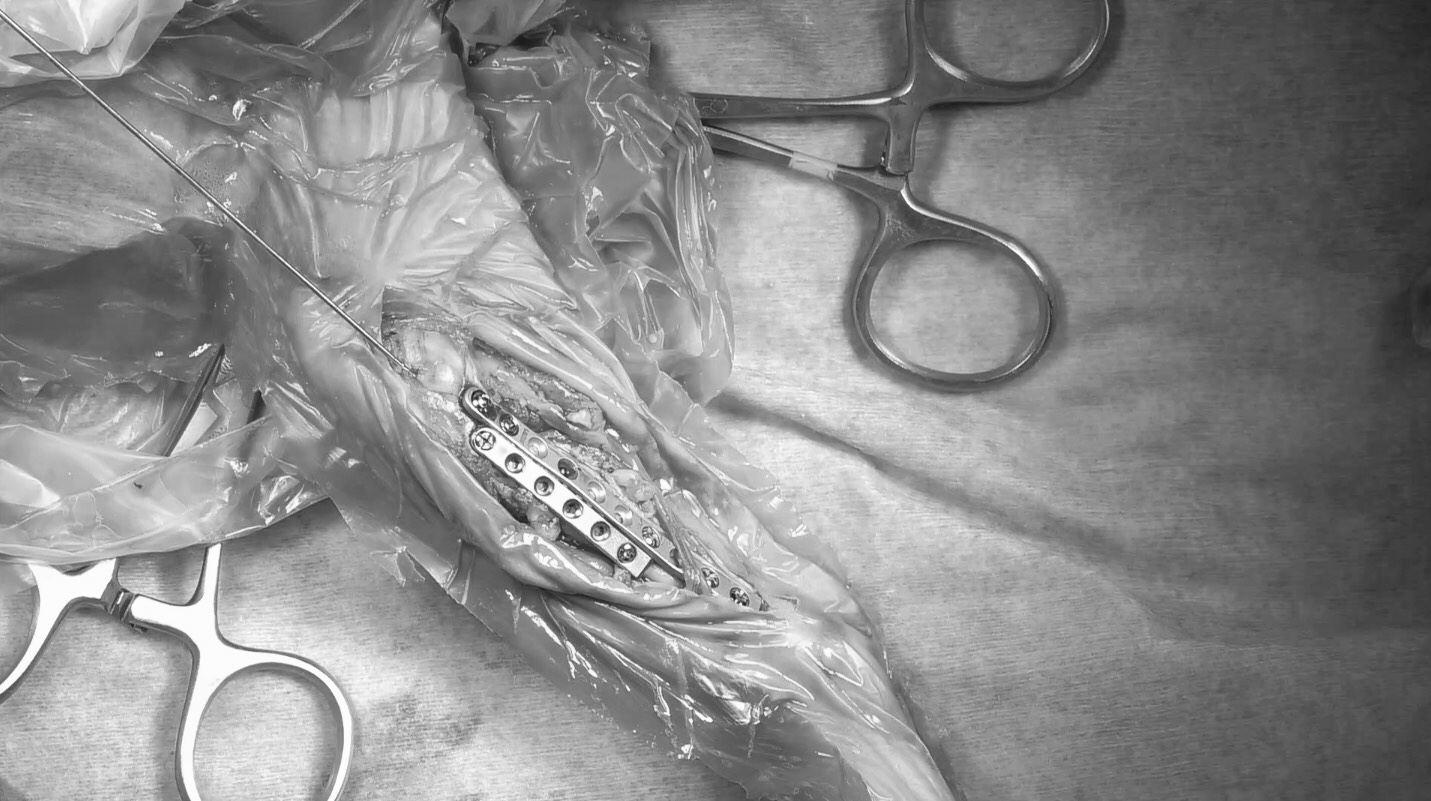

0.8㎜径のK-wireというピンを挿入して骨片の配置を整えた上で、内側面に1.5前内側面に1.3のプレートを設置し固定しました。